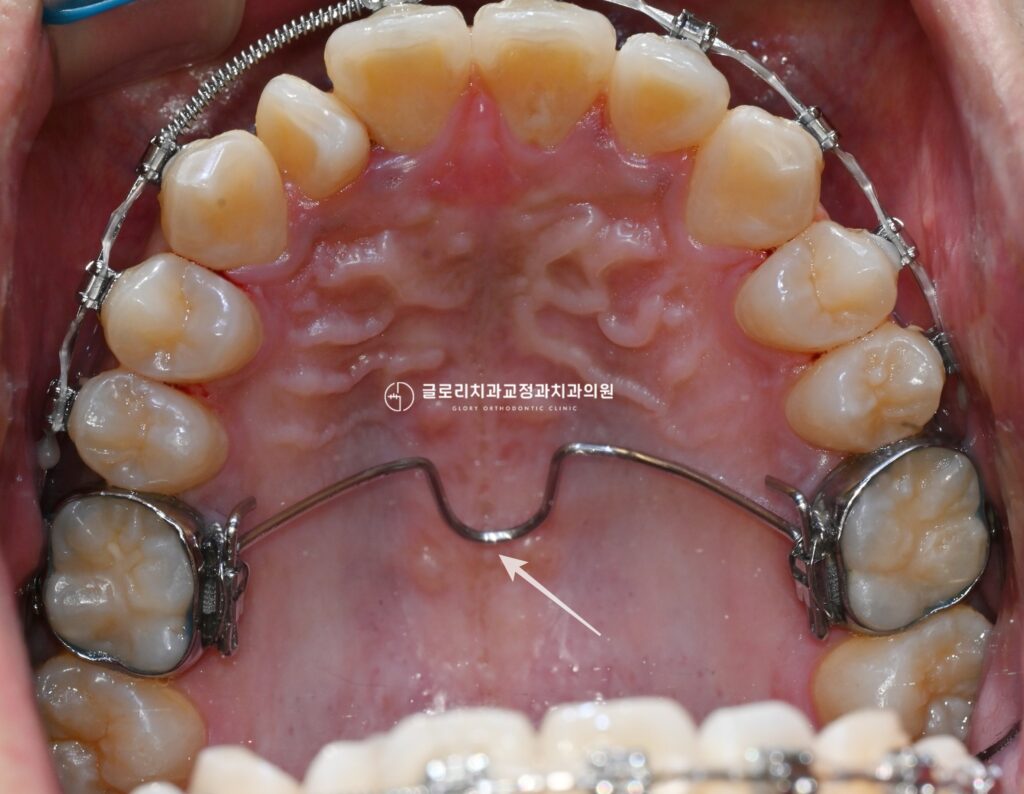

횡구개 호선

확장장치를 통해 치열궁의 폭경을 충분히 넓혀 공간을 확보한 이후에는 횡구개 호선을 적용할 수 있습니다.

횡구개 호선이란 상악 구치부를 연결하는 구개측 호선 장치로

확장된 악궁의 폭경을 유지하고 구치부가 다시 안쪽으로 좁혀지는 것을 방지하는 역할을 합니다.

또한 구치부의 고정원을 강화해 이후 브라켓 교정 시 치아 이동을 보다

효율적으로 조절할 수 있도록 도와주는 보조장치이기도 합니다.

상봉동 교정치과 에서 보여드리는 예시자료처럼 양측 상악 구치부에 밴드를 장착하고

그 사이를 굵은 호선으로 연결하는 구조로 이루어져있는데 장치 자체는 구개쪽에 위치하기 때문에

외부에서는 잘 보이지않으며 브라켓 교정과 함께 병행하게됩니다.